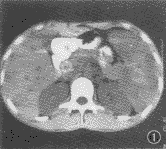

图1 CT平扫。脾脏显著肿大,脾内见多发性低密度灶,边界不清,后腹膜、腹主动脉周围多个淋巴结肿大,下腔静脉前方见淋巴结环状钙化